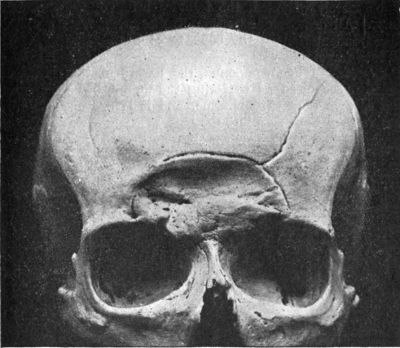

| 188. | Depressed Fracture of Frontal Bones with Fissured Fracture | 365 |

| 189. | Depressed and Comminuted Fracture of Right Parietal Bone: Pond Fracture | 365 |

| 190. | Pond Fracture of Left Frontal Bone, produced during Delivery | 366 |